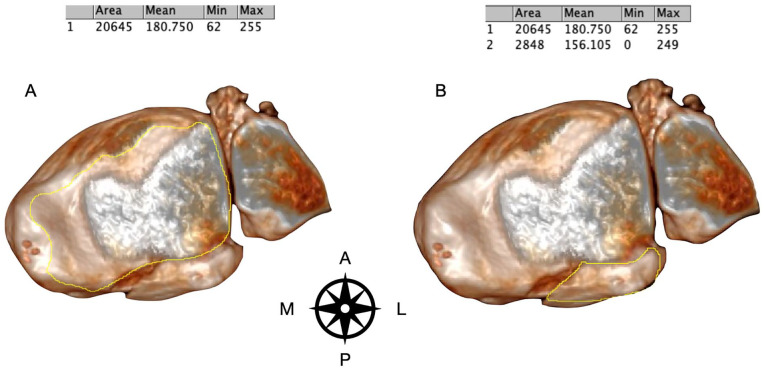

Methods: Morphology of the PMF was categorized initially by the CT scan as classified by Mason and Molloy on 180 trimalleolar ankle fractures. PM fracture fragment size on the lateral radiograph were compared to their respective 3D surface rendering CT reconstructions, by two independent observers. Morphology of the PMF was assessed using all preoperative radiographs as compared to 3D SR CT.

Results: On comparison of fracture fragment morphology, all fractures had poor categorization by plain radiographs although rotational pilon fractures (type 2A and 2B fractures) had the worse sensitivity and specificity (below 33% and below 50%, respectively). Radiographs underestimated joint involvement in type 2B fracture patterns because of the underappreciation of the posteromedial fragment.

Conclusion: This study shows that the use of plain radiographs to categorize morphology of PMFs is poor. The study adds to the ever-growing body of evidence on the inaccuracy of using plain radiographs in PMFs to plan treatment. Additional CT imaging is imperative to allow for appropriate treatment planning in the management of PMF. Smaller fracture fragments are more susceptible to inaccuracies, especially the rotational pilon subtypes (2A and 2B) because of the obliquity of the posteromedial fragment to the plane of the X-ray source.